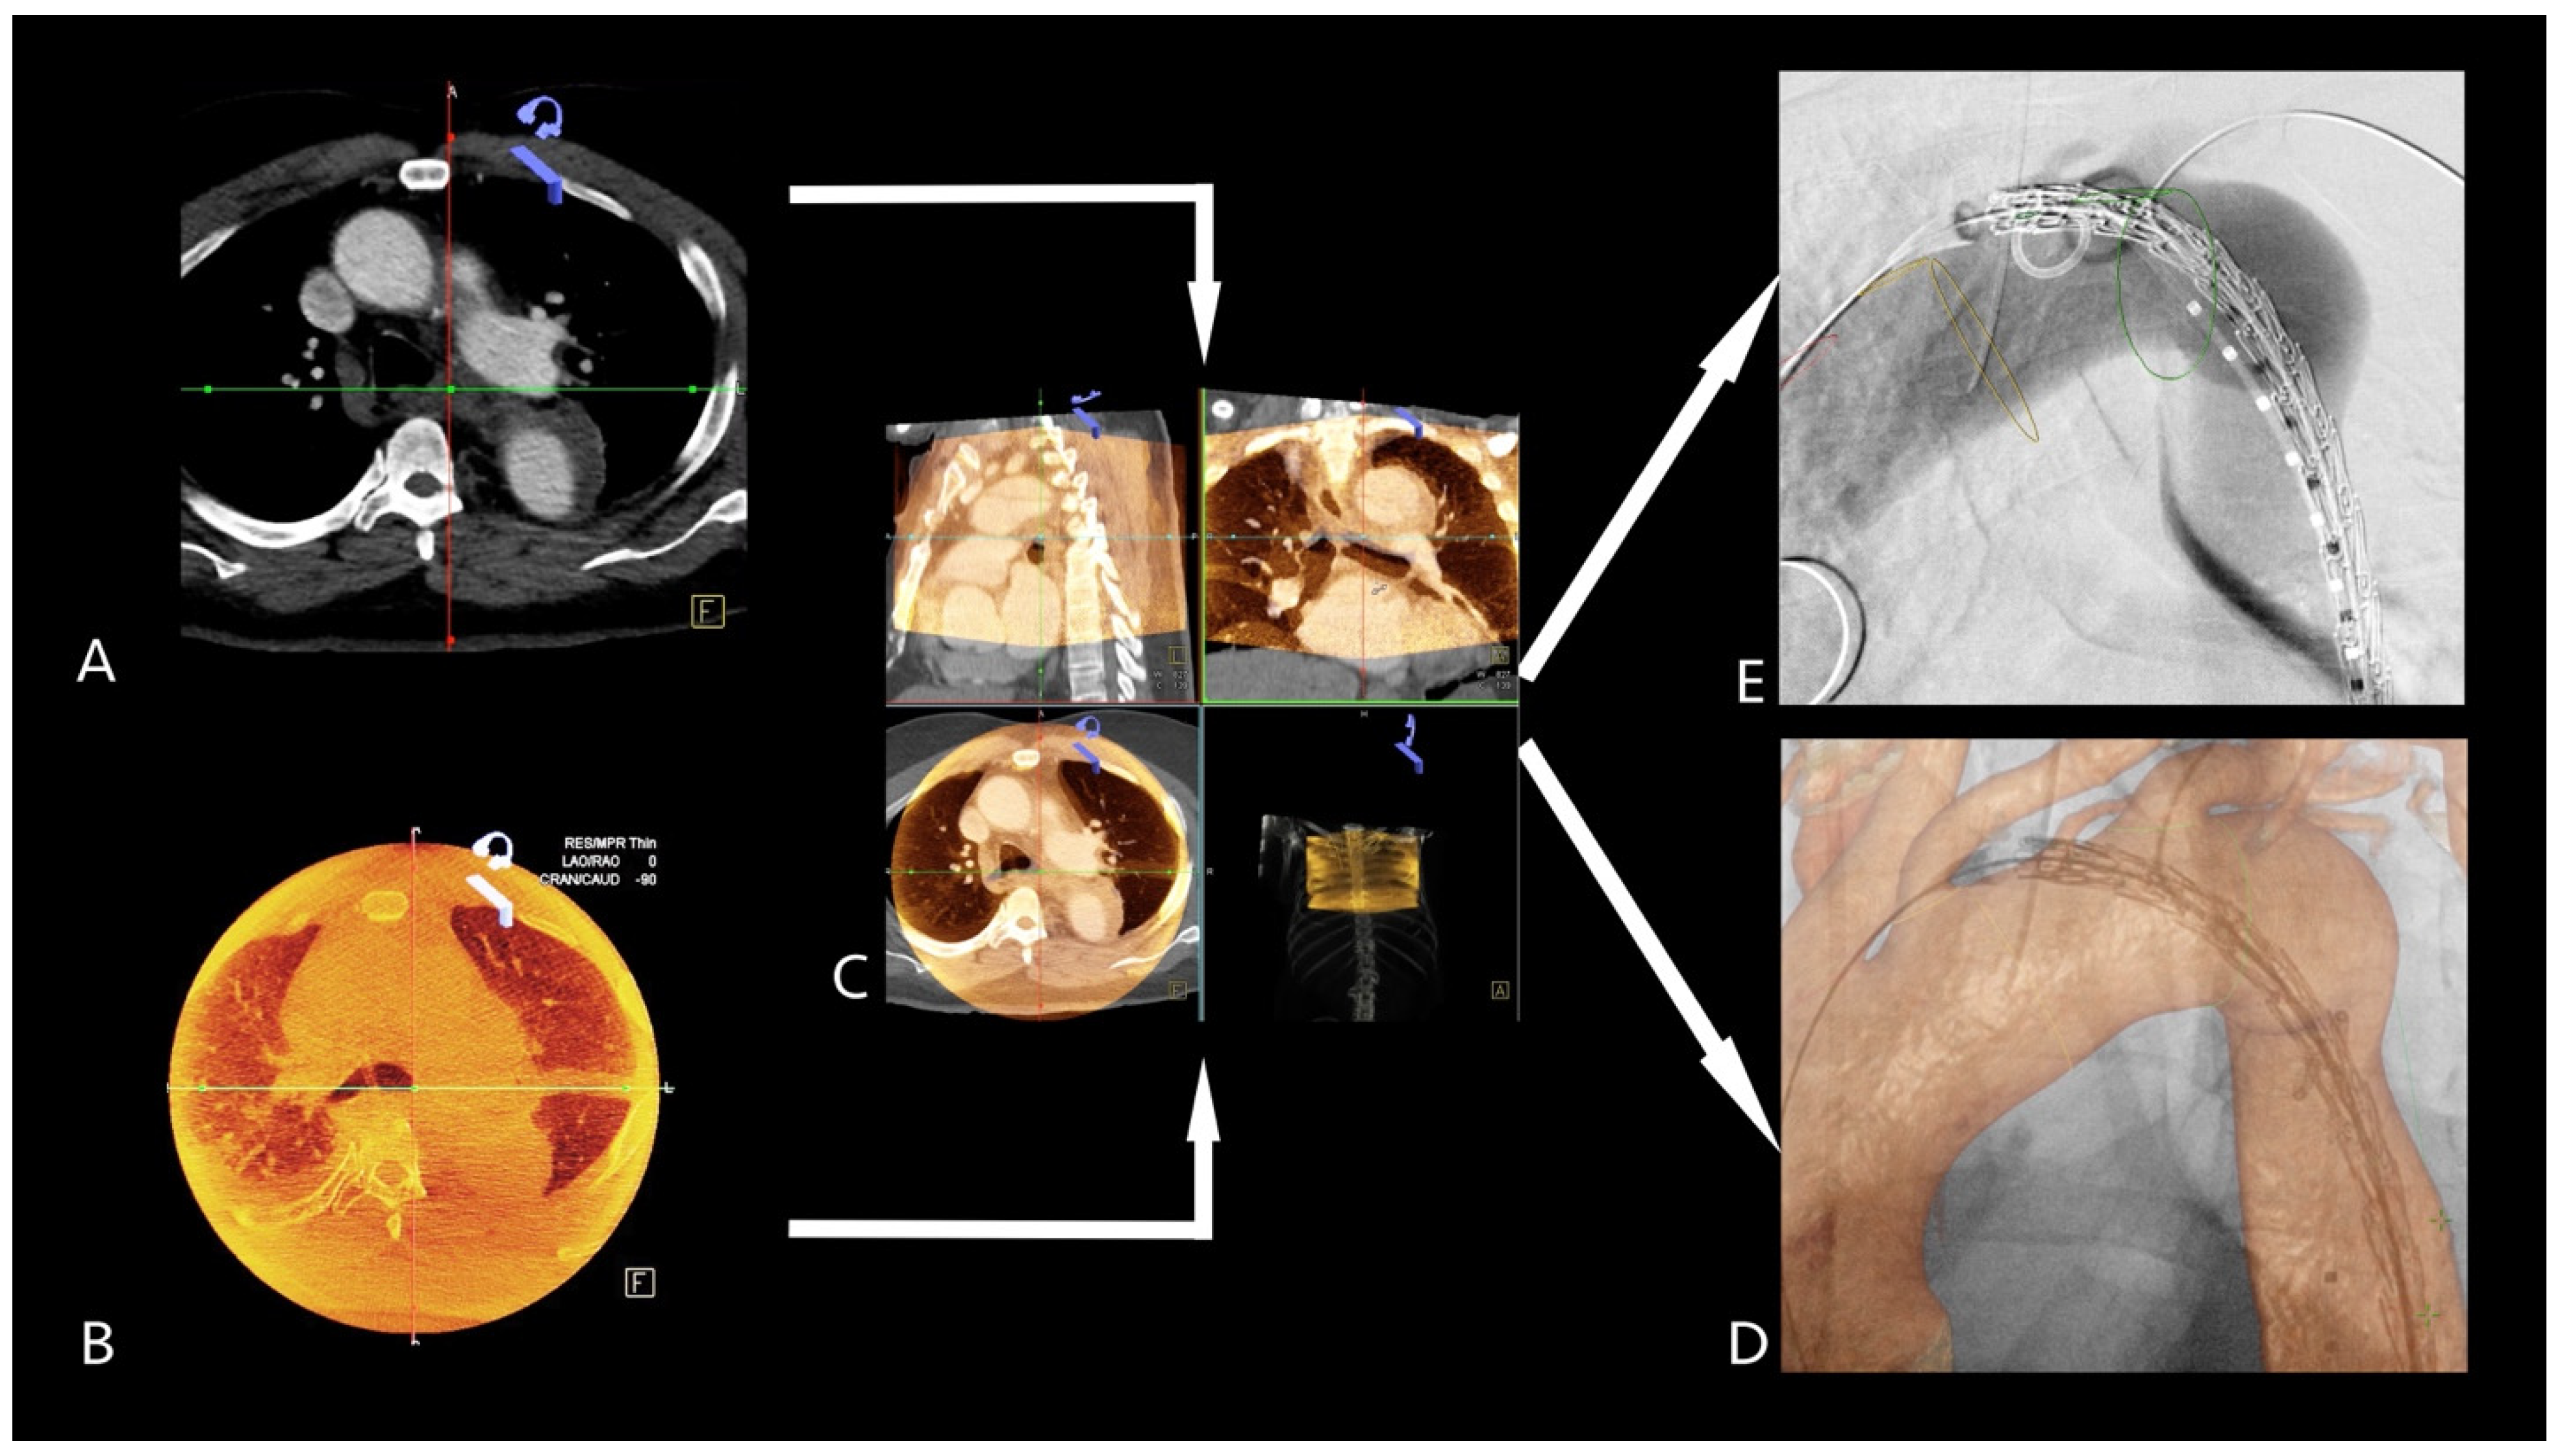

2.4. 2D3D Fusion Technique

2.5. 3D3D Fusion Technique